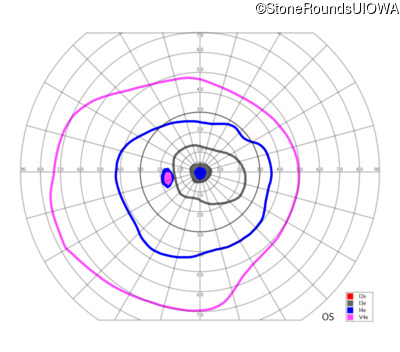

Congenital Stationary Synaptic Dysfunction (IA2g)

Congenital Stationary Synaptic Dysfunction (IA2g)

| Congenital Stationary Synaptic Dysfunction | CABP4 | Arg49Stop CGA>TGA | IVS1+1 G>T | AR |